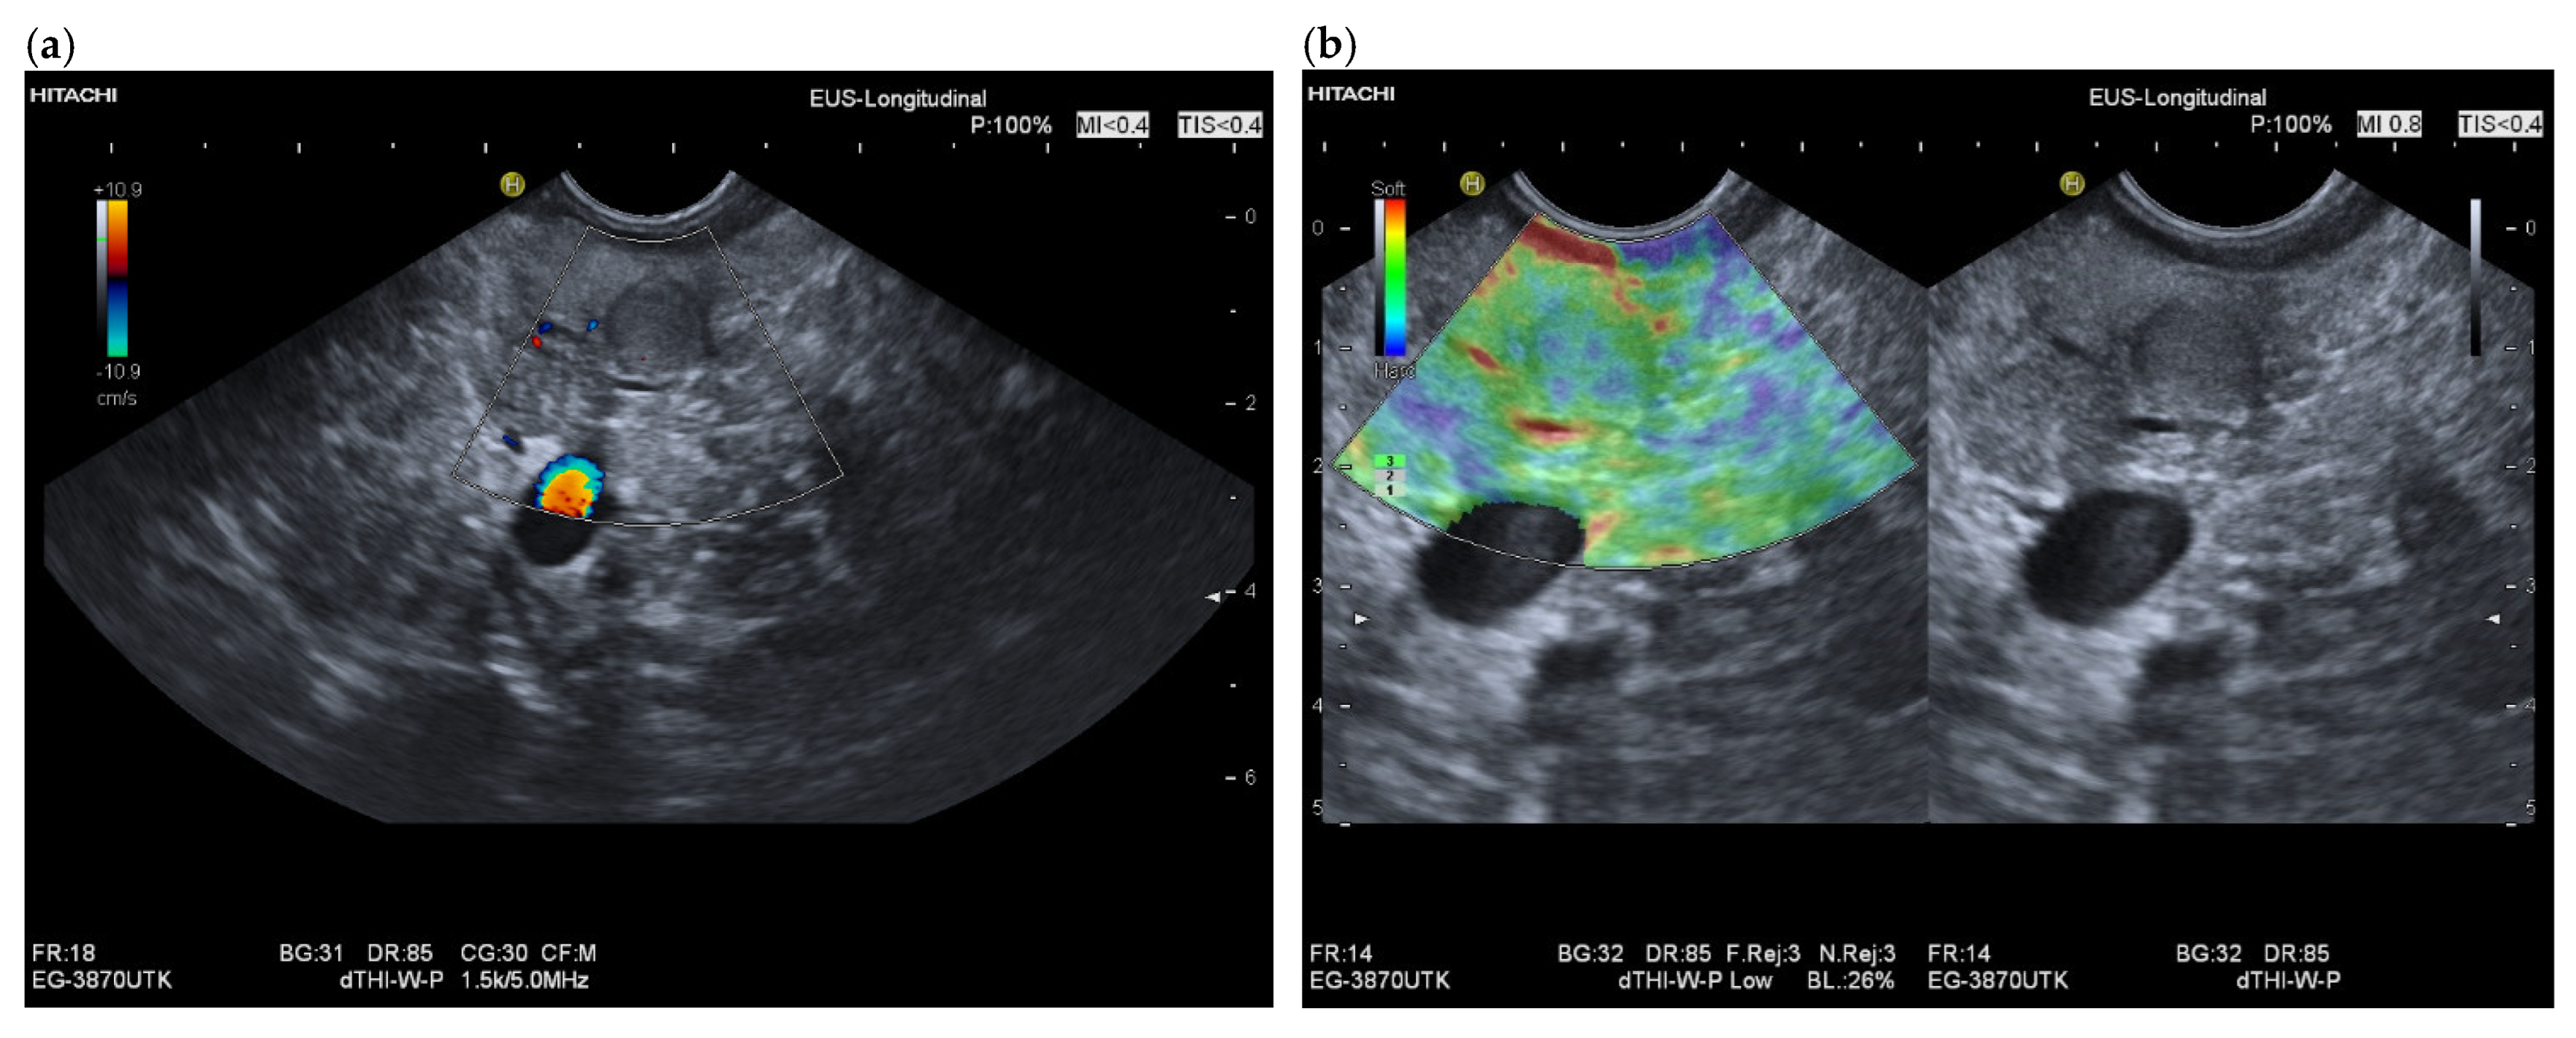

3.4. CEUS and CH-EUS

| Colour Doppler Imaging | RCC metastases are hypervascularized Most other pancreatic metastases are hypovascularized | No hypervascularization | Hypervascularized |

| Elastography (small lesions up to 15 mm) [67] | 41% softer or isoelastic, 59% stiffer compared to pancreatic parenchyma | 4% soft or isoelastic, 96% stiffer compared to pancreatic parenchyma | 64% soft or isoelastic, 36% stiffer compared to pancreatic parenchyma |